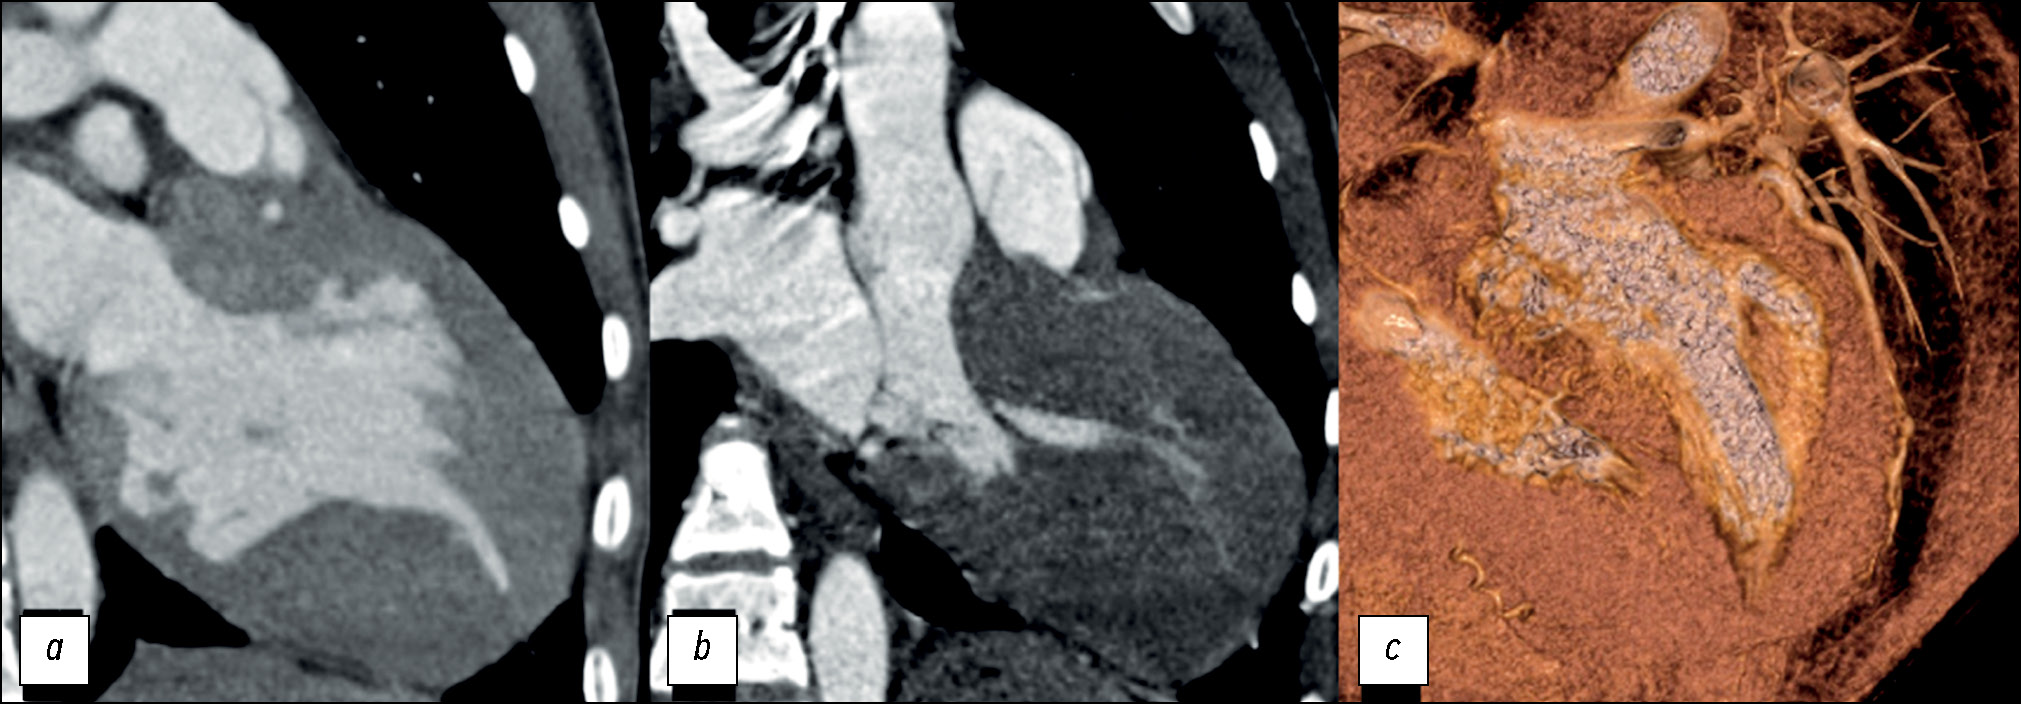

Среднежелудочковый фенотип выявлен у 5 из 47 (11%) пациентов (рис. 5), из них среднежелудочковый фенотип с апикальным выпячиванием/аневризмой ЛЖ выявлен у 2 (40%) пациентов.

Рис. 5. Пример MPR и 3D-изображений компьютерной томографии среднежелудочкового фенотипа гипертрофической кардиомиопатии с признаками систолической обструкции полости ввиду вариантной аномалии хордо-папиллярного аппарата и асимметричной гипертрофии миокарда левого желудочка: a — плоскость двухкамерной проекции левых отделов сердца; b — трёхкамерная проекция сердца; c — четырёхкамерная проекция сердца. Апикальное смещение заднебоковой папиллярной мышцы и прямой контакт с передней створкой митрального клапана; расщепление ножек сосочковых мышц + добавочная мышечная трабекула.

У 8 из 47 (18%) пациентов был выявлен ассиметричный вариант фокально-базального фенотипа ГКМП с S-образной/«сигмовидной» МЖП, характеризующийся гипертрофией миокарда перегородочных сегментов на базальном уровне вблизи ВОЛЖ (рис. 6).

Рис. 6. Пример 3D-изображений компьютерной томографии фокально-базального фенотипа гипертрофической кардиомиопатии: a — плоскость двухкамерной проекции левых отделов сердца; b — короткая ось сердца. ЛЖ — левый желудочек; ЛП — левое предсердие; ПЖ — правый желудочек; МЖП — межжелудочковая перегородка; Ао — аорта.

У 4 из 47 (8%) пациентов выявлен концентрический фенотип, характеризующийся симметричной гипертрофией стенок ЛЖ с уменьшением полости. Еще 4 (8%) пациента соответствовали апикальному фенотипу (рис. 7).

Рис. 7. Пример MPR и 3D-изображений компьютерной томографии пациента с апикальным фенотипом гипертрофической кардио-миопатии после имплантации кардиовертер-дефибриллятора: a — плоскость четырёхкамерной проекции; b — двухкамерная проекция левых отделов сердца; c — 3D VRT реконструкции четырёхкамерной проекции сердца.